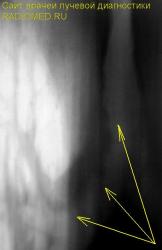

Очень смутило перибронхиальное уплотнение, помеченное жёлтыми стрелками.

3.jpg